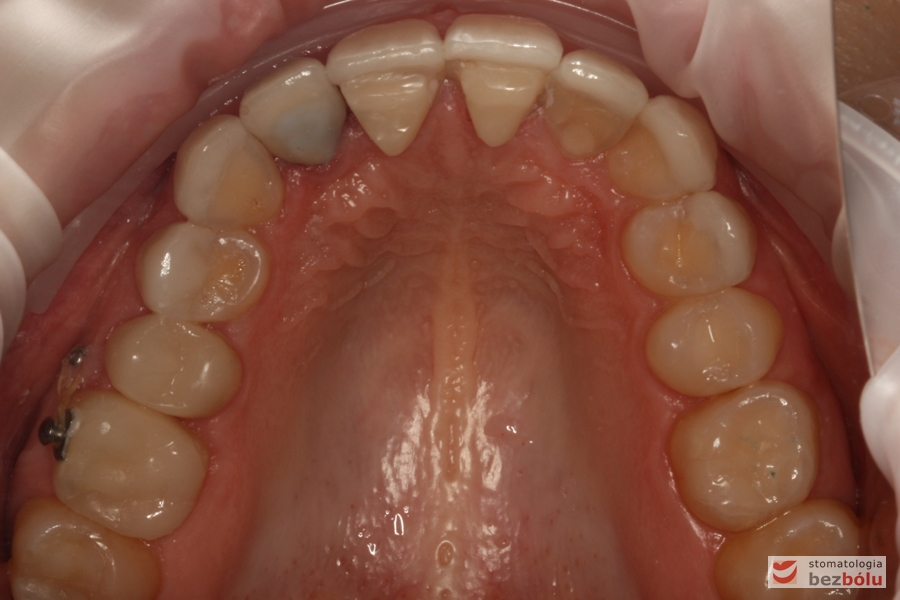

Szczęka - widok okluzyjny, nieregularny kształt łuku zębowego, metal na dwójce górnej

Szczęka – widok okluzyjny, nieregularny kształt łuku zębowego, metal na dwójce górnej